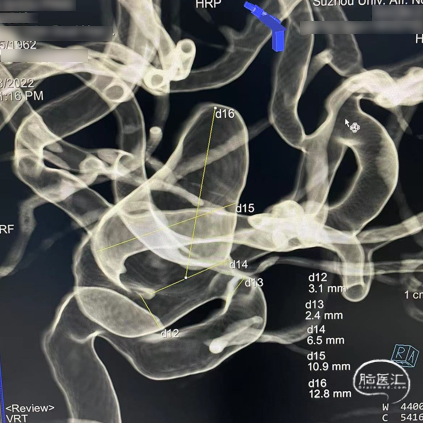

左侧颈内动脉眼动脉段动脉瘤

术前影像

诊断:左侧颈内动脉眼动脉段动脉瘤,动脉瘤瘤体直径12.8mm,瘤颈直径6.5mm,载瘤动脉远端直径3.3mm,近端直径3.5mm;密网支架落脚于近端较为平直段血管处,直径略大。

处理策略:弹簧圈1枚,1枚如意SM*FDD-425-25mm治疗。